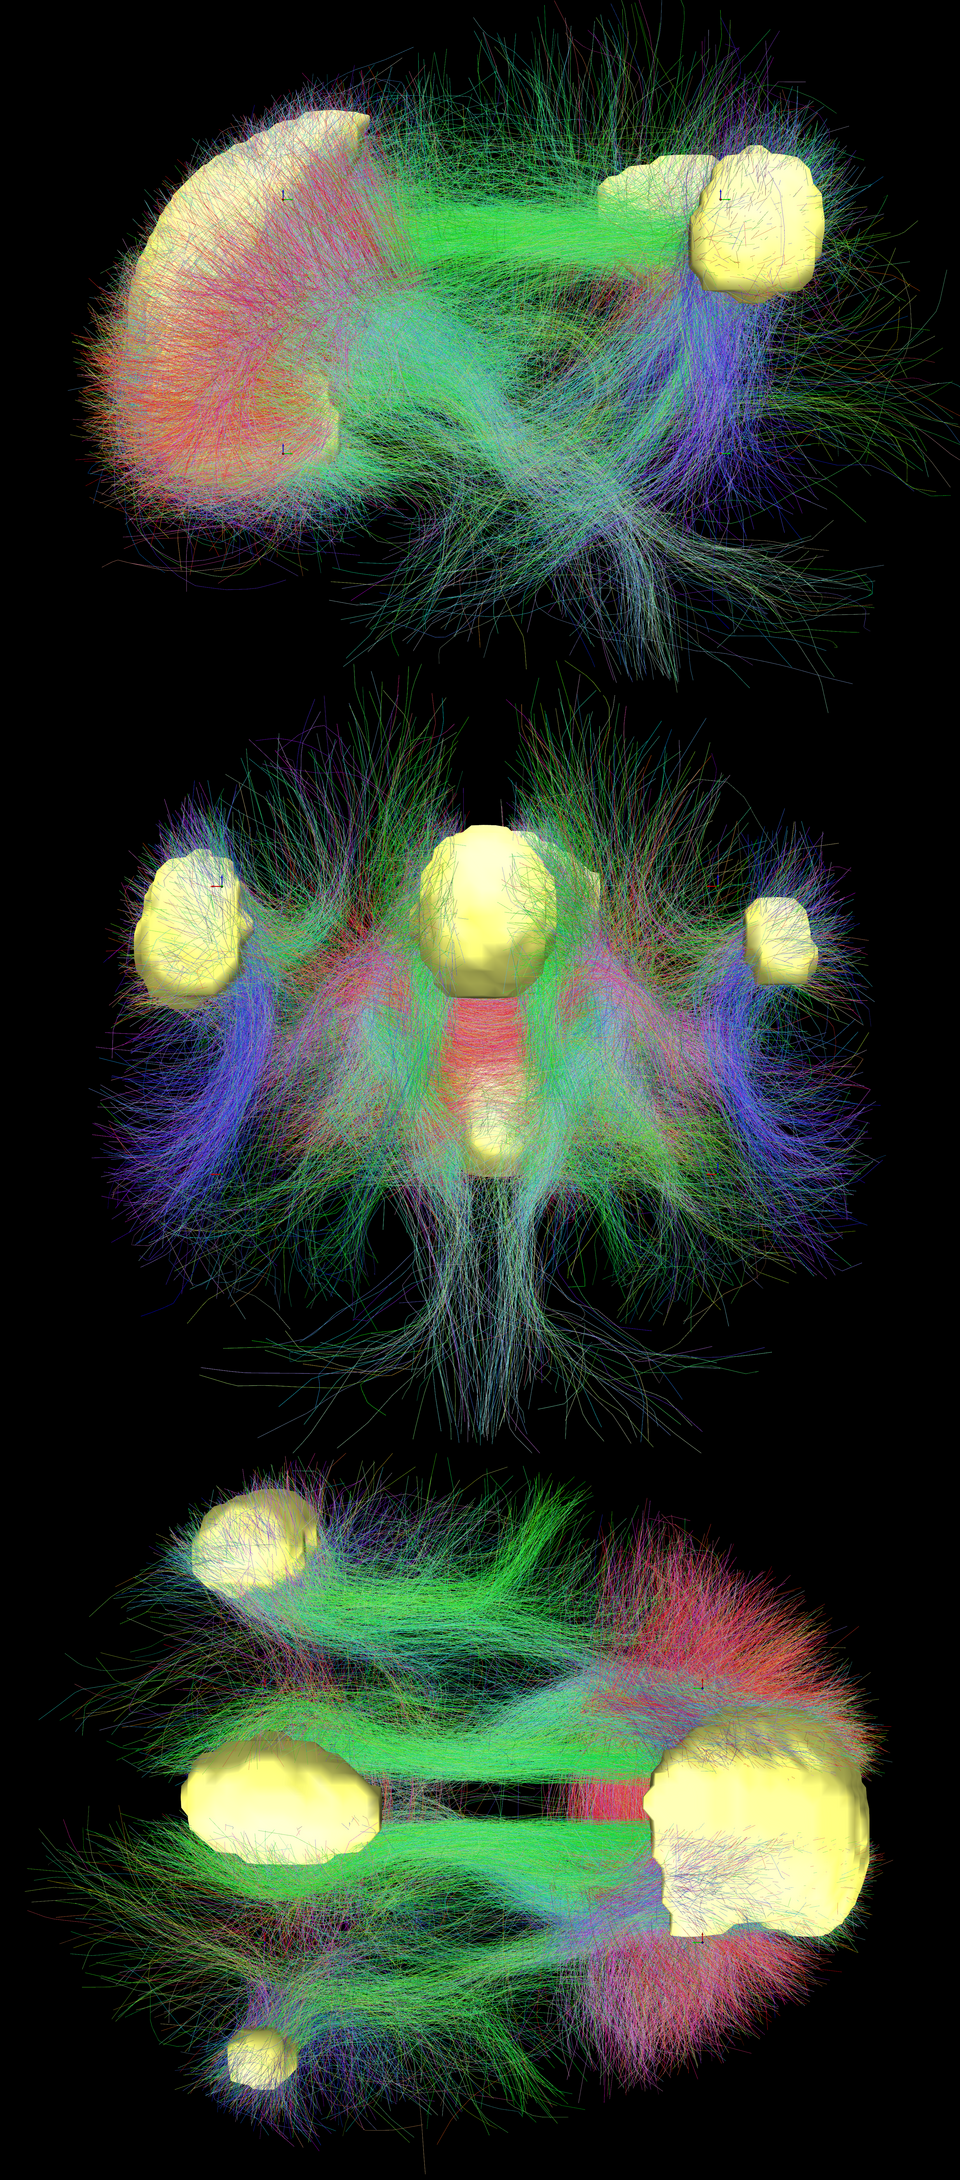

DMN regions

Default Mode Network regions from a literature review.

DMN connectivity

Main regions of the DMN (yellow) and connectivity between them color-coded by structural traversing direction (xyz → rgb).